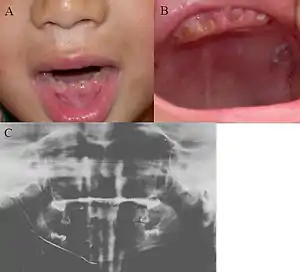

| Oral photographs from an individual with Dentinogenesis imperfecta | |

Dentinogenesis imperfecta (DI) is a genetic disorder of tooth development. This condition is a type of dentin dysplasia that causes teeth to be discolored (most often a blue-gray or yellow-brown color) and translucent giving teeth an opalescent sheen.[1] Although genetic factors are the main contributor for the disease, any environmental or systemic upset that impedes calcification or metabolisation of calcium can also result in anomalous dentine.

Clinical appearance is variable with presentation ranging from gray to yellowish brown, but the characteristic feature is the translucent or opalescent hue to the teeth.